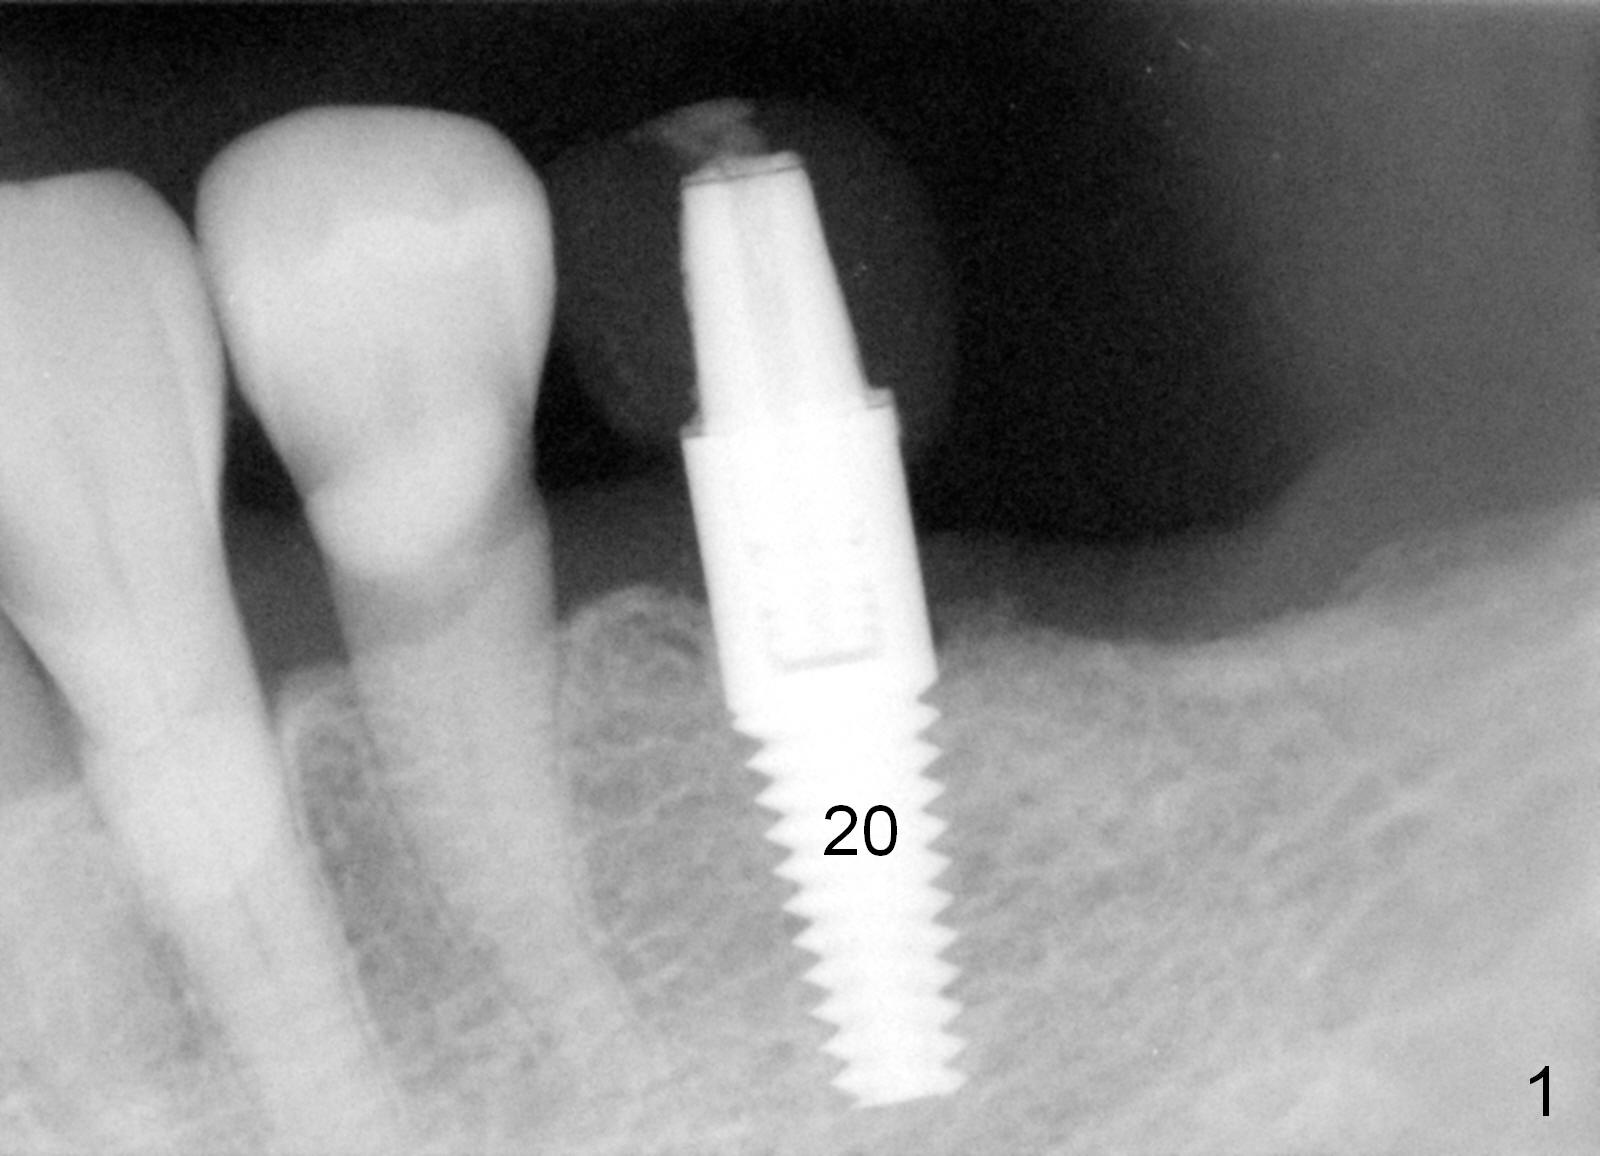

Last visit, a 76-year-old lady found that the tooth #24 was mobile. After #25 implant crown recementation, occlusal equilibrium was done so that occlsual force/contact was transferred from #24 to #25. Two weeks later, the tooth #24 mobility is reduced. The patient wants to crown the rest of the lower anterior teeth. After discussion, she agrees to restore the posterior teeth first. PAs and impression are taken (Fig.1-4). When the implant was placed at the site of #20 (Fig.1), the bone was found to be soft. To obtain primary stability, osteotomy at #18 and 19 will be under prepared (one size smaller). The immediate provisional at the site of #20 is oversized mesiodistally. Before surgery, it should be trimmed as shown in Fig.4 red dashed line. The 3 implants are to be splinted. No localized use of antibiotic is for this case, since these 2 teeth have been missing > 6 months.